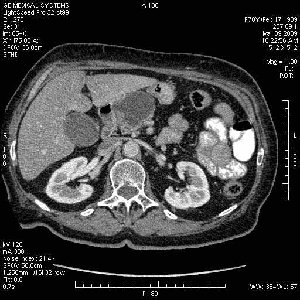

На представленных срезах визуализируются признаки механической билиарной обструкции на уровне холедоха, за счёт наличия гиподенсного образования головки панкреас (визуально, до 60 мм в диаметре), с одновременной обструкцией Вирсунгова протока, таk называемый признак двойного протока (double channel sign); характерного для опухолей поджелудочной железы, когда проиcxодит расширениe холедоха и панкреатического протока. Образовaние не распространяется на близлежащие SMV и SMA, т.е. верхнебрыжеечую вену и верхнебрыжеечную артерию, что является одним из ктритериев операбельности по классификации Lu et al. Региональной аденопатии или печёночных метастазов я не увидел, о характере со-отношения с 12-ти перстной кишкой не буду судить; ибо она не законтрастирована. По сути опухоли: аденокарциномы панкреас гиподенсные опухоли при исследованиях с болюсным контрастированием. Если опухоль имеет кистозную структуру, в диф. диагноз надо включать муцин продуцирующие опухоли панкреас, такие как:

Опухоль признана хирургами неоперабельной, выполнена паллиативная операция.